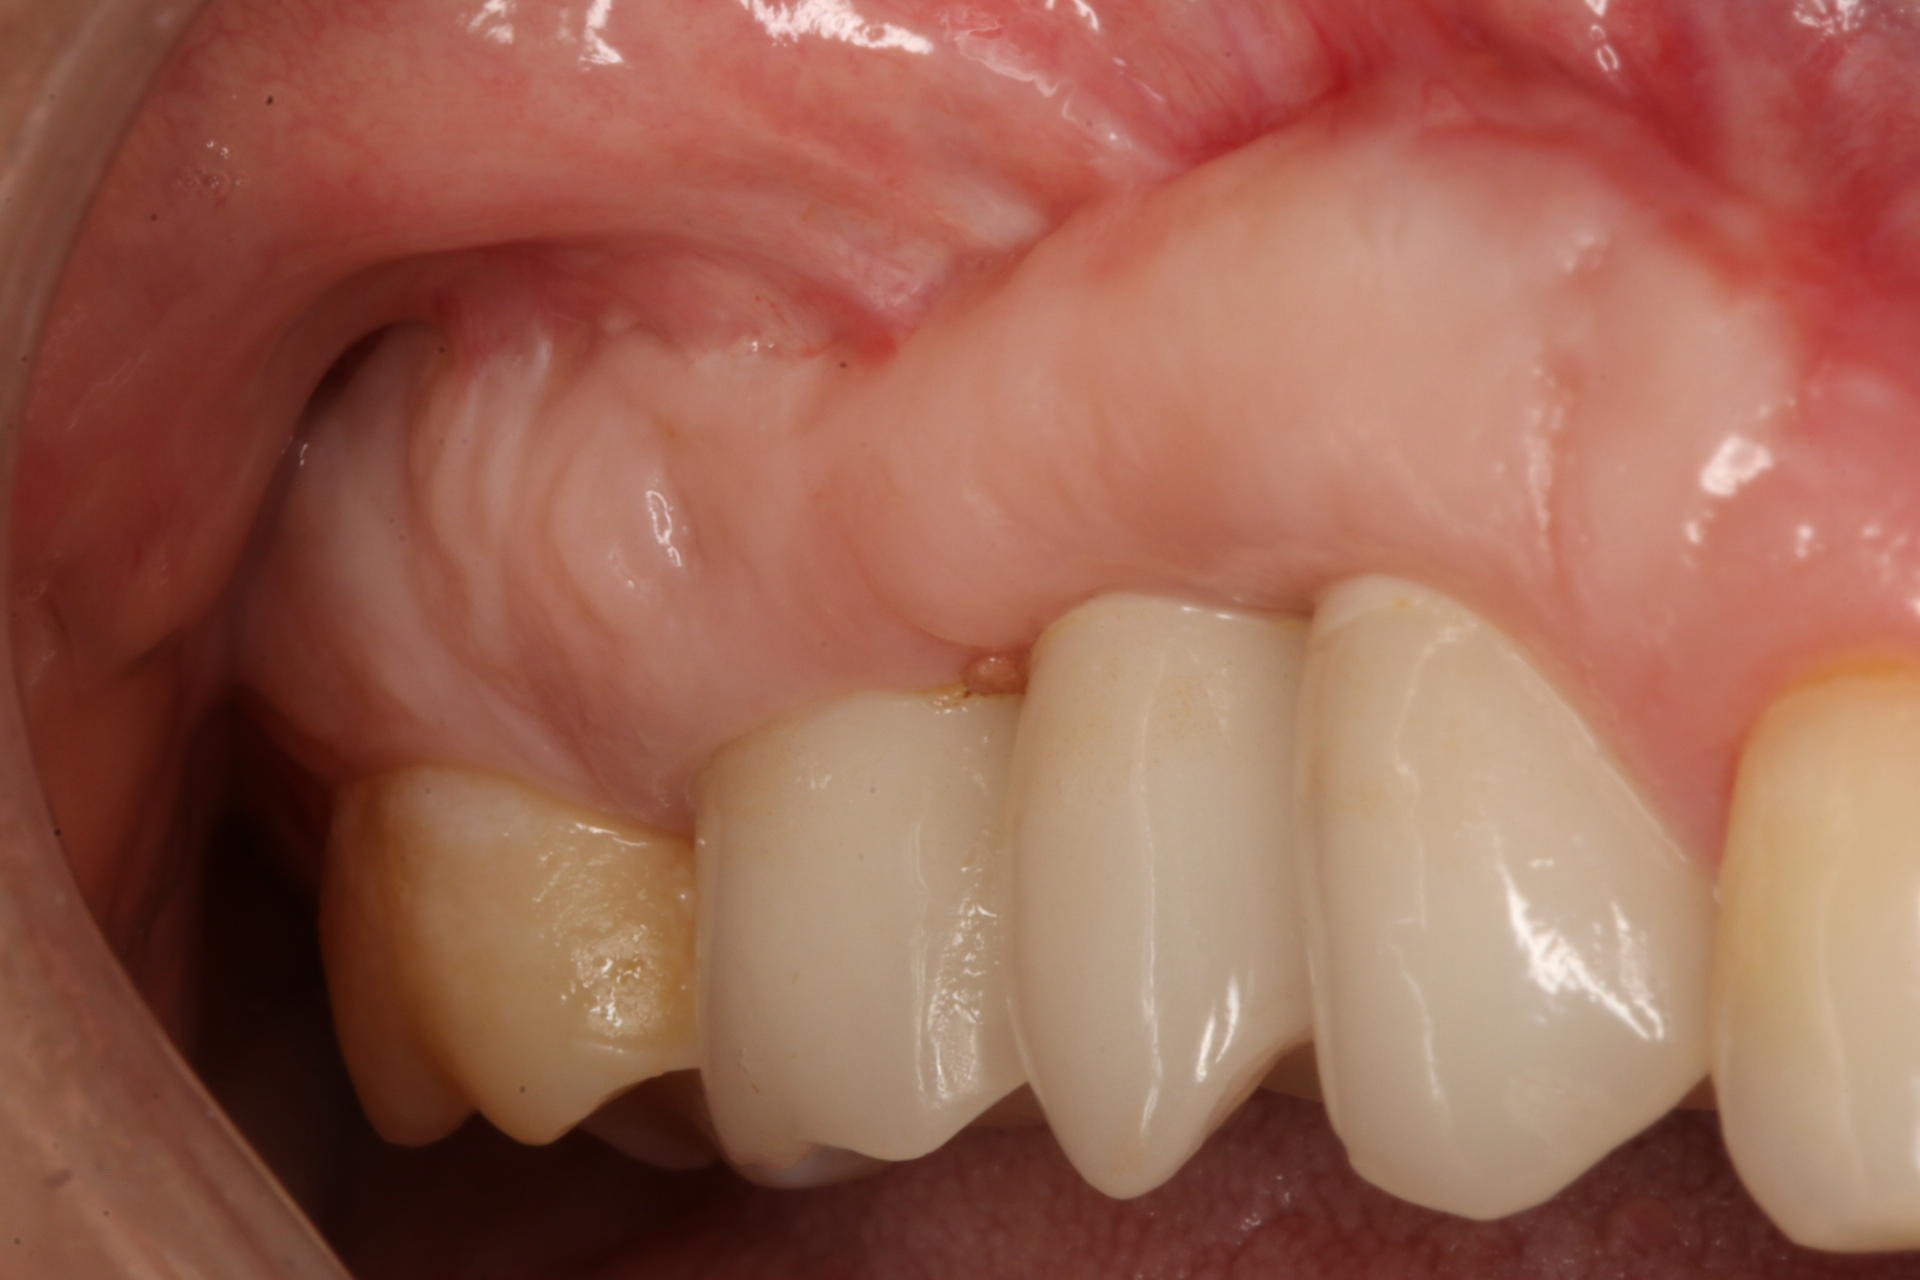

• Contour grafting around implants - the Keys to your success

• Esthetic zone strategies

Dinner: The Esthetic Zone Magic Bullets that you must have to maximize your chances of success